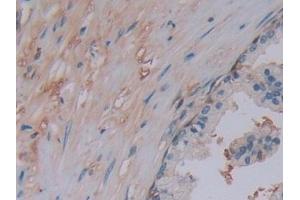

CHAT 适用: 人 WB, IHC, ICC, IP 宿主: 兔 Polyclonal unconjugated

产品编号 ABIN7440704

CHAT 适用: 人 WB, IHC 宿主: 兔 Polyclonal unconjugated

产品编号 ABIN3016135

CHAT 适用: 人, 小鼠, 大鼠 WB, IHC 宿主: 兔 Polyclonal unconjugated

Pubmed 7 references

产品编号 ABIN5518818